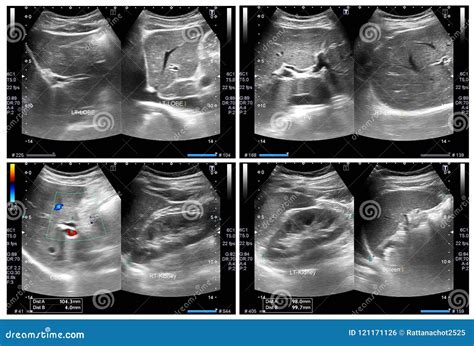

• Kidneys: Examining the kidneys for stones, tumors, cysts, or other abnormalities.

• Kidney Stones: The location and size of kidney stones can be determined.